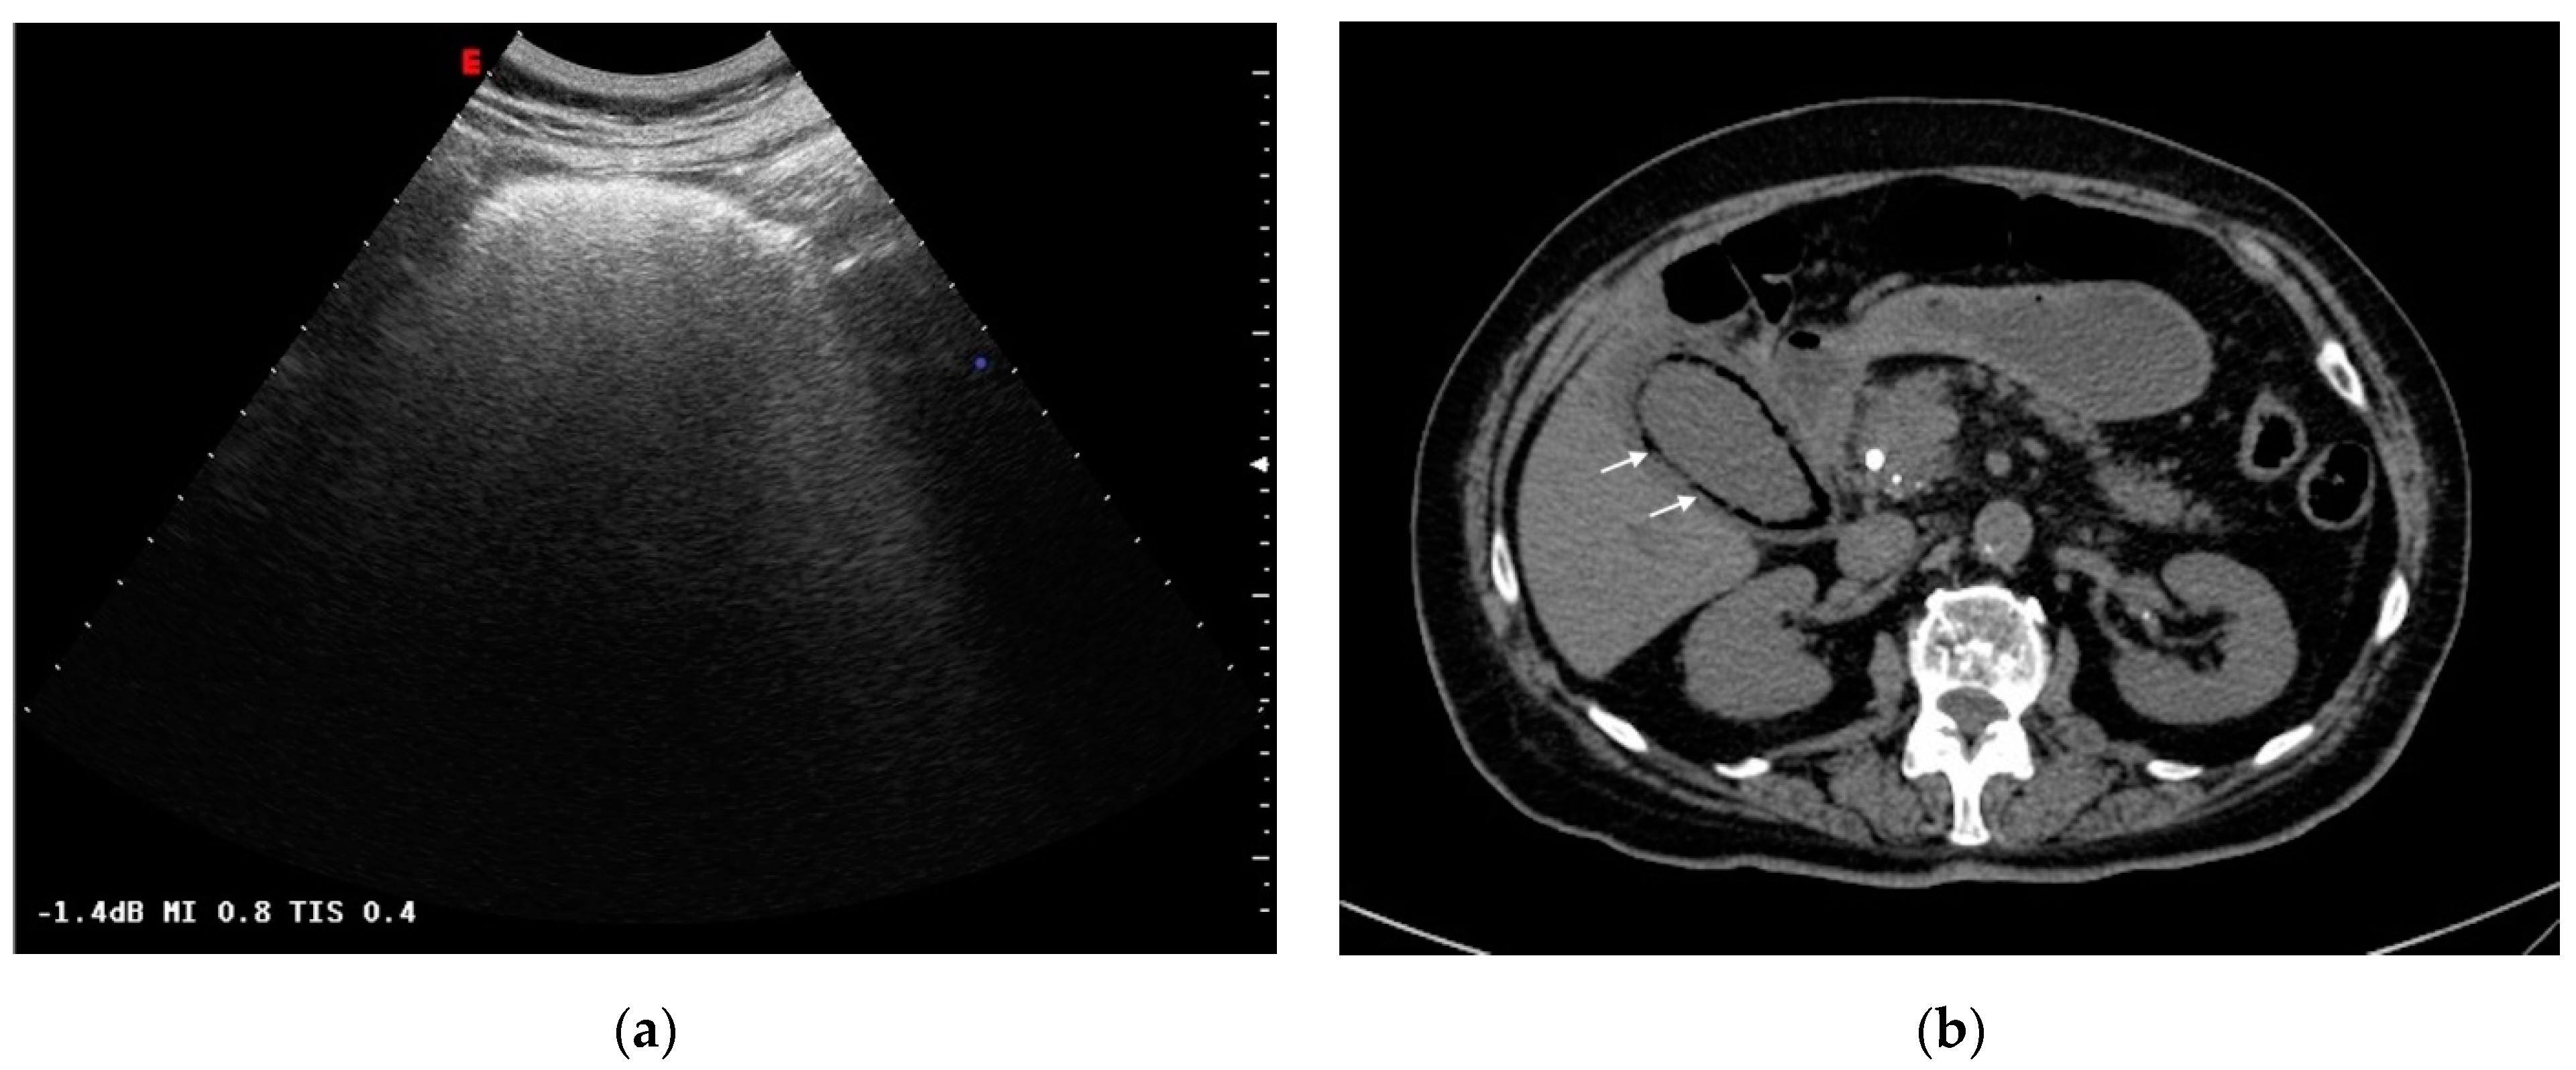

Figure 3.

Emphysematous cholecystitis: (a) Ultrasonography: diffuse hyperechogenicity due to extended reverberation artifact with poor gallbladder lumen resolution. (b) CT findings: gallbladder wall thickening with intramural air (white arrows). CT was able to detect and characterize the disease.